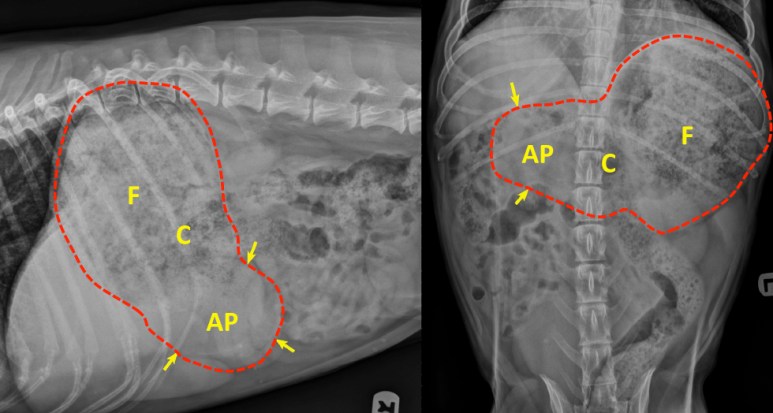

Il était facile de tomber dans le piège avec ce chien et suspecter une masse pylorique, hépatique ou splénique. L’opacité de tissu mou arrondie aux contours lisses (flèches jaunes) représente l’antre pylorique (AP) remplie de liquide alors que le chien est placé en décubitus latéral droit. L’air remonte dans le corps (C) et le fundus (F) pour mettre en évidence la nourriture qui y est aussi présente. Une échographie a quand même été réalisée en raison de cette incertitude et des signes cliniques, pour ne révéler aucune anomalie. Le chien a répondu aux traitements symptomatiques de base.

L’image du bas illustre le déplacement du liquide et de l’air en fonction du décubitus latéral. Comme le liquide se retrouve dans l’antre pylorique (AP) lorsque le chien est placé sur son côté droit, l’opacité résultante peut facilement mimer une masse plus ou moins sphérique en fonction de la taille et de l’orientation de l’antre. D’autant plus que le liquide se confond à la paroi digestive (comme sur l’image). À l’opposé, en décubitus latéral gauche, l’air remonte dans l’antre pylorique située plus dorsalement, facilitant son identification sur une latérale gauche. C’est aussi pour cette raison qu’une latérale droite est préconisée lors de volvulus gastrique pour mettre en évidence l’antre pylorique déplacée du côté gauche. E, oesophage. D, duodénum.